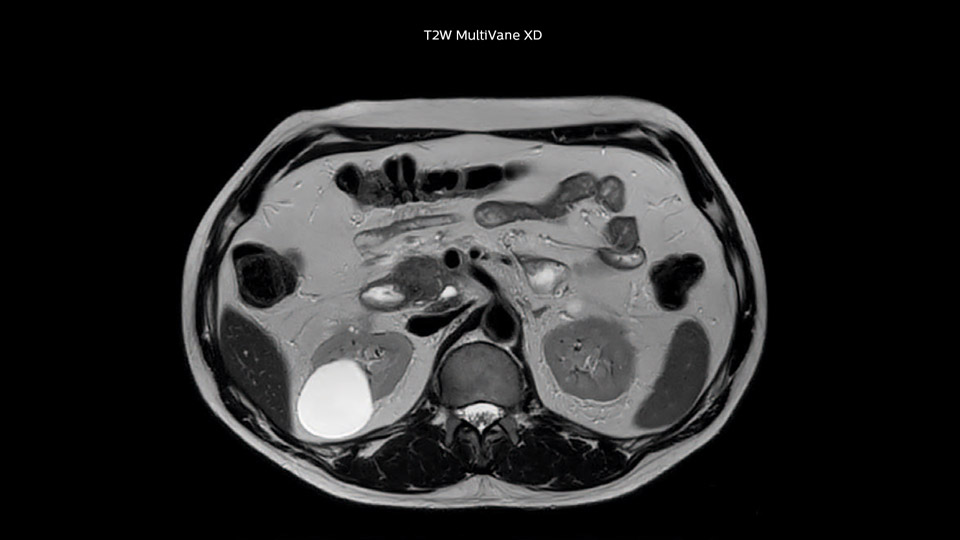

Dr. Baumann then implemented MultiVane XD for motion correction. It uses an extended reconstruction algorithm for imaging that is virtually motion free. “With MultiVane XD we get excellent motion-corrected images with high spatial resolution. We typically first optimize our scan for high image quality, and when satisfied with that, we try to reduce the scan time. So, we combined MultiVane XD with dS SENSE, which allows us to shorten the scan time,” he explains. “The performance of MultiVane XD in liver imaging is outstanding. MultiVane XD with dS SENSE is a powerful development in improving liver image quality.” “As we use breathhold imaging for T2-weighted liver scans, we depend on the patient’s ability to cooperate with the exam. This can present a real challenge when we are looking for small lesions, such as in our oncological patients. However, with MultiVane XD motion correction, we get excellent images. This is important for our surgeons, because they want to know exactly where the lesions are.”

In this example the image quality of the MultiVane XD images is evidently better than in the images without MultiVane XD. Ingenia 1.5T with dS Torso coil solution.

“Our liver exams are quite fast,” says Dr. Baumann. “If the patient tolerates it, we use an arms-up position to reduce the FOV and speed up the exam with dS SENSE.” “We acquire one transversal high resolution T2-weighted sequence with 3 mm slice thickness, for example for pancreas or liver lesions. Then we also add a T2 fat suppressed MultiVane XD SPIR sequence. We perform these two routinely in our liver imaging. We use high dS SENSE factors to significantly shorten scan times to 2-4 minutes, which can improve our protocol; it’s a very robust scan.” “We include mDIXON for the dynamic sequences because of the robust and homogeneous fat suppression we get with that. We had been using eTHRIVE, but we are now quite happy with mDIXON. Sometimes we use a medication to calm the bowels, to further improve the image quality.”

“I would absolutely recommend to other sites to implement MultiVane XD with dS SENSE in their abdominal cases, as it’s brilliant for robust, motion-corrected abdominal imaging. It provides us with excellent image quality with high resolution in a short time,” says Dr. Baumann. “I would advise using MultiVane XD for T2 and T2 fat suppressed high quality imaging for almost every liver case.”